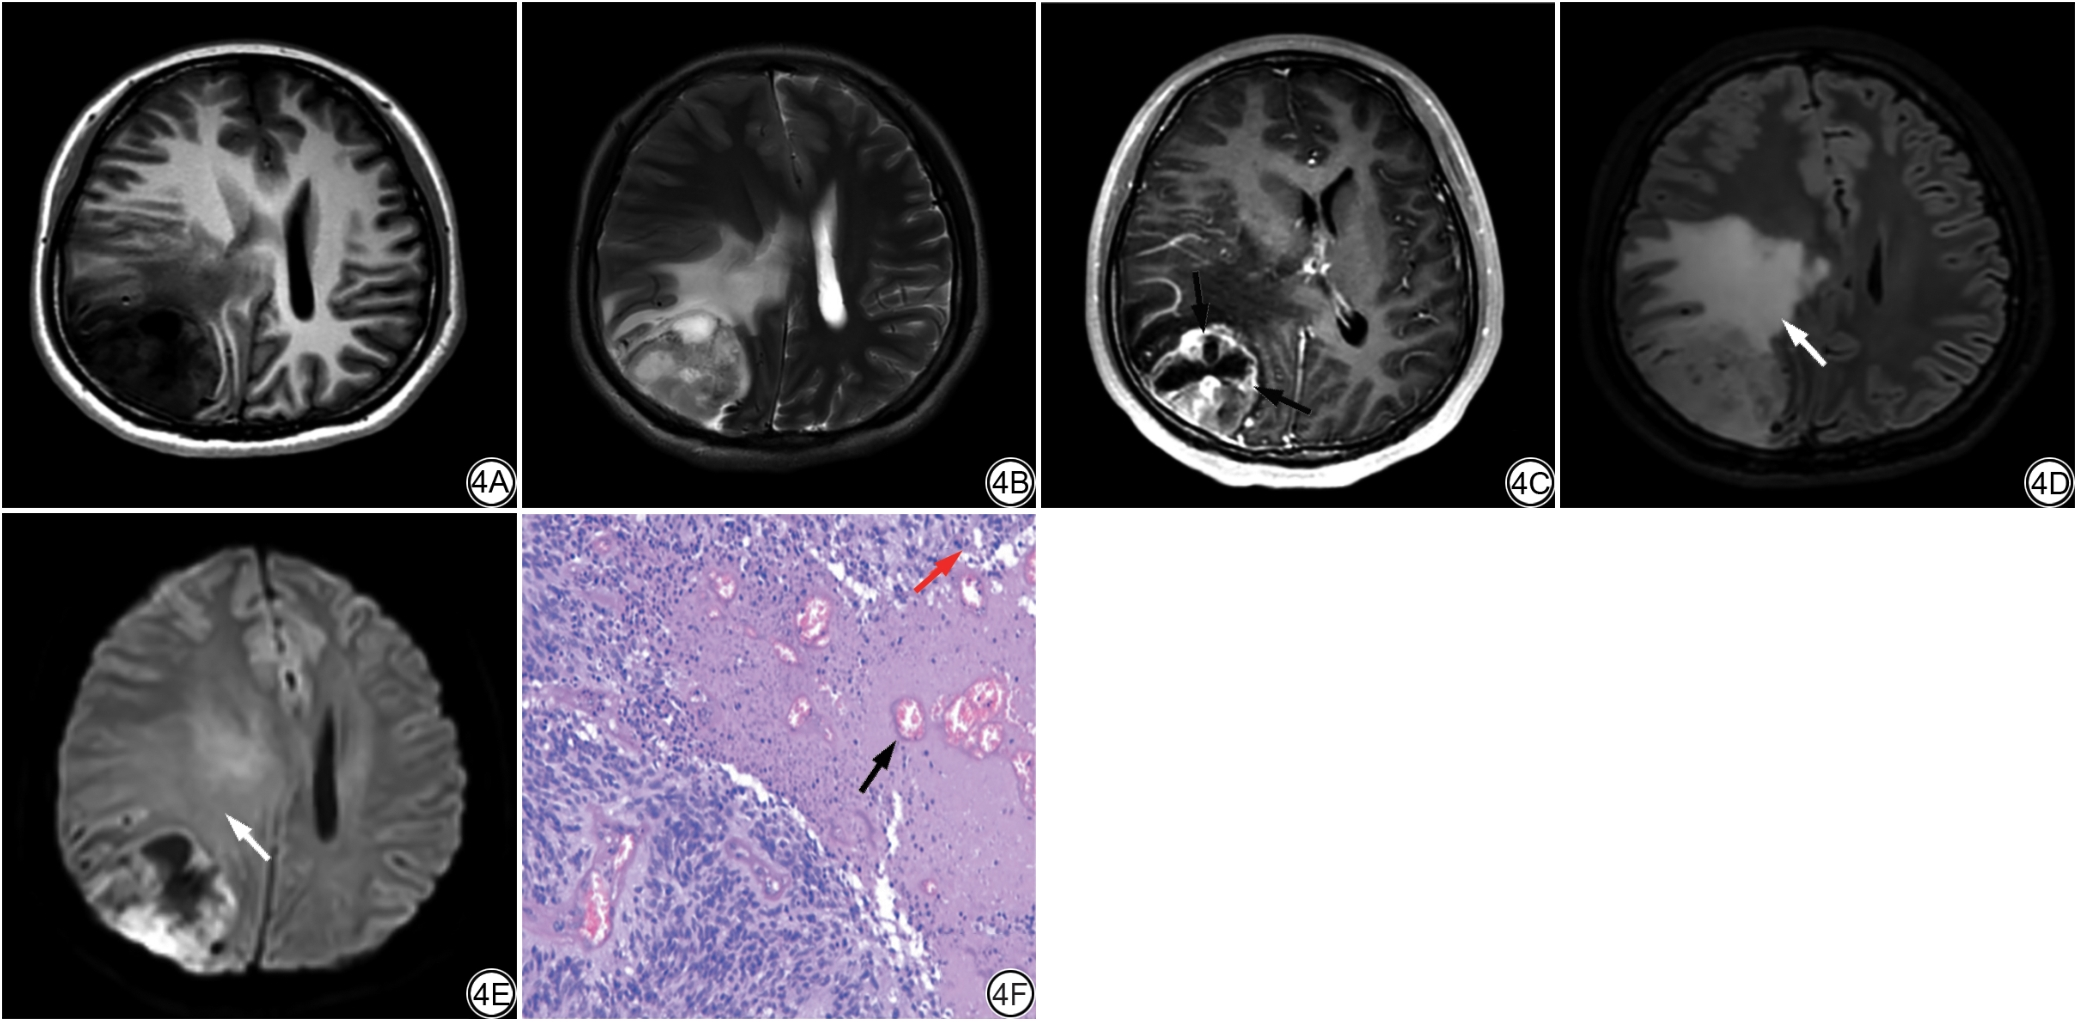

图 3  女,17岁,右侧额叶IEE,WHO分级2级,Ki-67增殖指数5%(低表达),VASARI总分为70。3A~3B分别为T1WI、T2WI图像,病灶呈囊性,表现为长T1长T2信号影,边界清楚、信号不均匀,其内见多发线样分隔影;3C:CE-T1WI图像,肿瘤囊壁及其内分隔强化,囊内容物未见强化,强化边缘(F11,箭)厚度为薄(3分);3D~3E分别为FLAIR、DWI图像,瘤周弥漫斑片状水肿影,FLAIR呈高信号,DWI呈等信号,瘤周水肿(F14,白箭)百分比为34%~67%(5分);3F:病理图(HE ×200)可见肿瘤细胞呈放射状围绕血管分布,形成假菊形团结构(黑箭)。IEE:颅内脑室外室管膜瘤;VASARI为伦勃朗视觉感受图像;CE-T1WI:增强T1加权成像;FLAIR:液体衰减反转恢复成像;DWI:弥散加权成像。

Fig. 3  Female, 17 years old, with right frontal lobe IEE, WHO Grade 2, Ki-67 proliferation index 5% (low expression), and a VASARI total score of 70. 3A-3B: T1WI and T2WI images show a cystic lesion with long T1 and long T2 signalintensity, clear margins, and heterogeneous signal. Multiple linear septations are visible within the lesion. 3C: CE-T1WI image demonstrates enhancement of the tumor cyst wall and internal septations, with no enhancement of the cyst contents. The thickness of the enhancing margin (F11, arrow) is thin (3 points). 3D-3E: FLAIR and DWI images reveal diffuse patchy edema around the tumor. The edema appears hyperintense on FLAIR and isointense on DWI. The percentage of peritumoral edema (F14, white arrow) is 34%-67% (5 points). 3F: Histopathological image (HE × 200) shows tumor cells arranged radially around blood vessels, forming pseudorosette structures (black arrow). IEE: intracranial extraventricular ependymoma; VASARI: visually accessible Rembrandt images; CE-T1WI: contrast-enhanced T1-weighted imaging; FLAIR: fluid-attenuated inversion recovery; DWI: diffusion-weighted imaging.